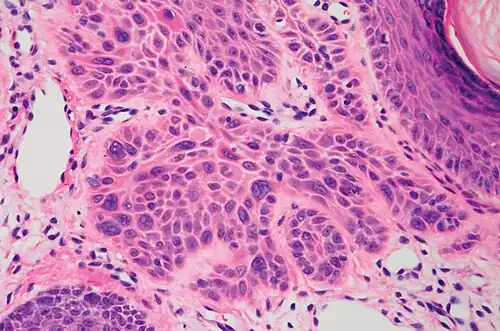

Invasive disease

In invasive cSCC, tumor cells infiltrate through the basement membrane. The infiltrate can be somewhat difficult to detect in the early stages of invasion: however, additional indicators such as full-thickness epidermal atypia and the involvement of hair follicles can be used to facilitate the diagnosis. Later stages of invasion are characterized by the formation of nests of atypical tumor cells in the dermis, often with a corresponding inflammatory infiltrate.[12]

-

High magnification demonstrates the pleomorphism of the invading keratinocytes[12] -

Invasive nests with characteristic large celled centers. Ulceration (at left) is common in invasive cSCC.